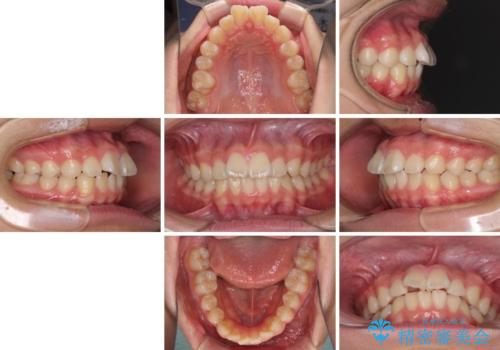

- 上下前歯のデコボコを改善したいとのことで来院された患者様です。

自己管理を減らしたいとのことで、ワイヤー装置による矯正治療を行うこととしました。

中学生と言うこともあり、1年強の短期間で終了しました。

歯磨きがしっかりとできないと虫歯になるリスクがありましたが、治療期間中は清潔な状態を保っていただけました。